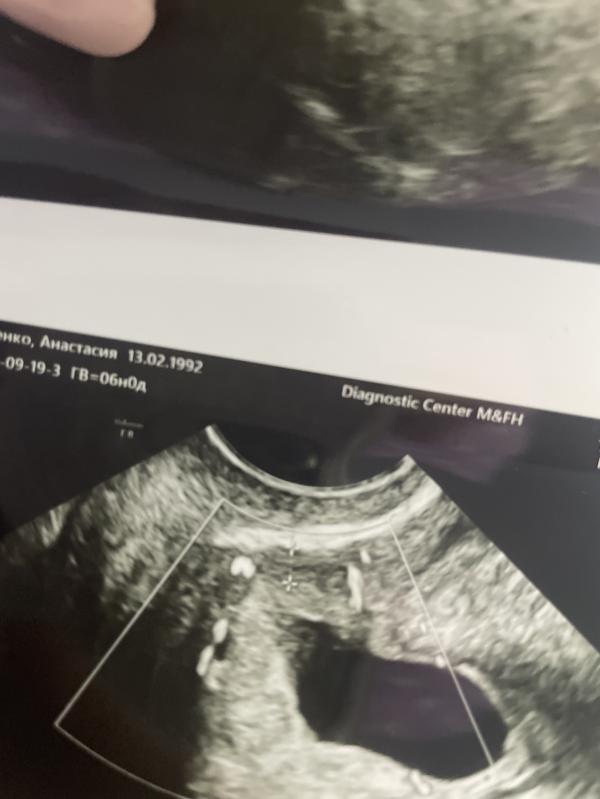

Всем привет, была на узи….

Срок 6.2, сердечко послушала❤️

Это из хорошего🙏🏻

Теперь не очень хорошее(((

Плодное яйцо в области рубца от кс….у кого было похожее, как проходила беременность, как прошли роды?